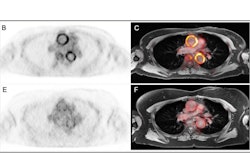

PET images were interpreted for FDG uptake to signal inflammation, while delayed-enhancement MR images were reviewed to determine any thickening of the aortic wall and luminal narrowing and dilation. The researchers targeted 11 arterial segments: four aortic segments, right and left common carotid arteries, right and left subclavian arteries,vertebral arteries, and common iliac and femoral arteries. Within those segments, they looked for three particular patterns in the PET/MRI results:

- Inflammatory patterns with positive FDG uptake in PET images and abnormal MRI with stenosis and/or wall thickening

- Fibrosis patterns with negative FDG uptake in PET images and abnormal MRI stenosis and/or wall thickening

- Normal patterns with negative results in both modalities